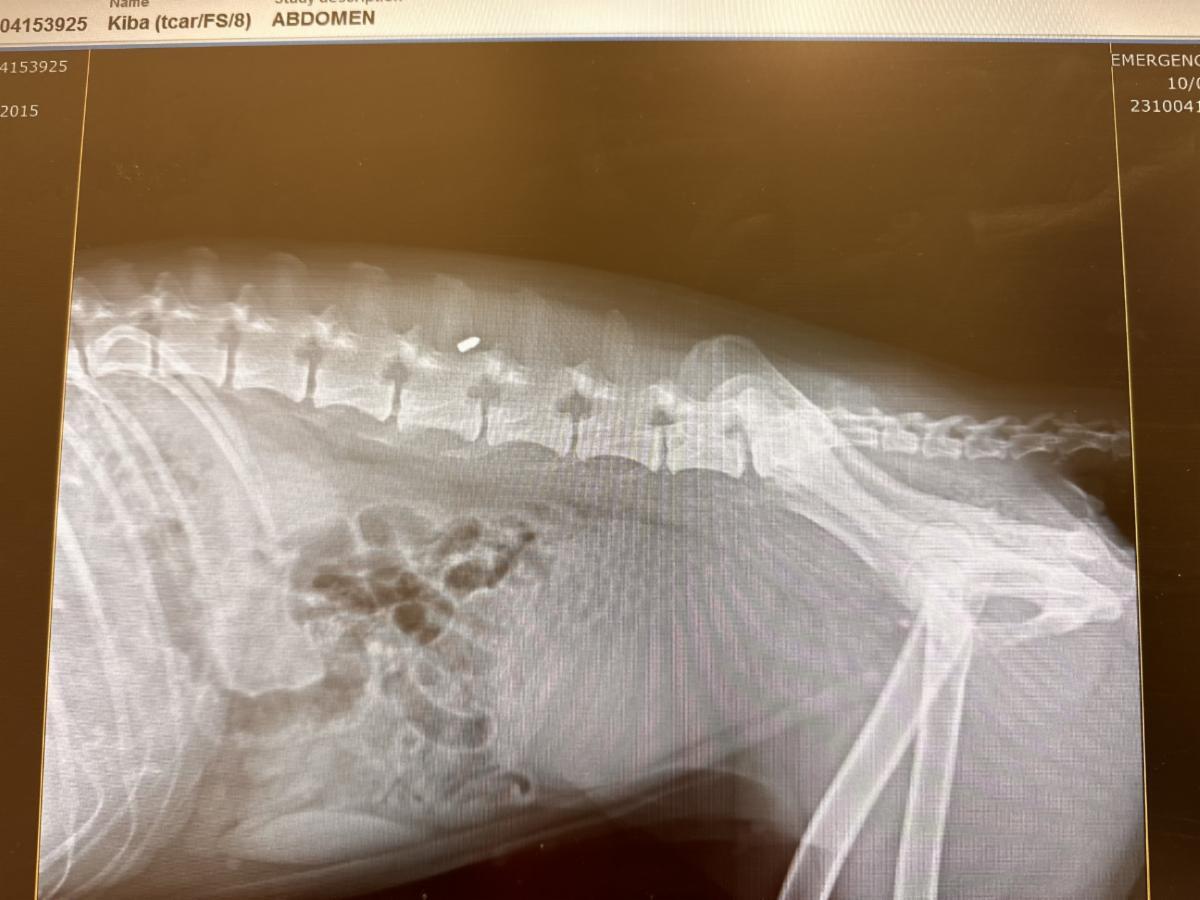

Kiba had surgery on Thursday to remove the metal pellet that was lodged near her spine and Swampland Husky Rescue in Gainesville said Tri-County Animal Rescue is covering her bill along with VCA Palm Beach for her neurology consult, images and fluids.

Swampland Husky Rescue said Kiba she is completely paralyzed and lacks feeling in her hind legs. She is also incontinent and needs to wear briefs. The organization said a pair of wheels has been donated and they are hoping she may walk again.